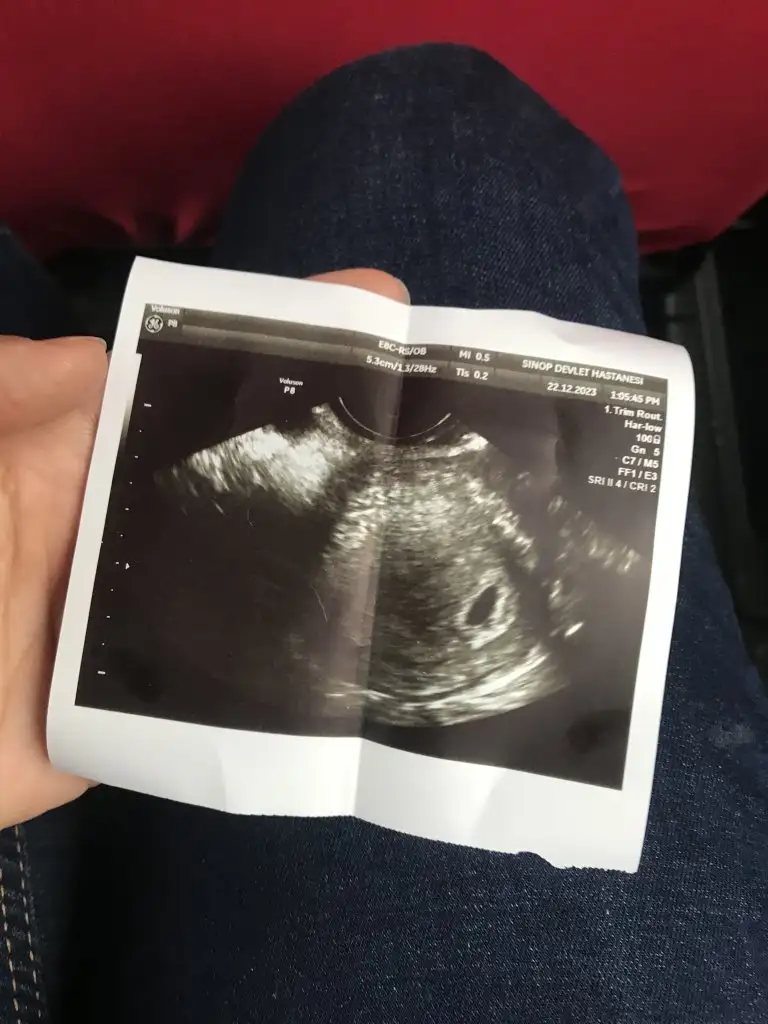

9 haftalıktan 12 haftalığa kadar koydum canım bende çok merak ediyorum cevabını bekliyorumSelam Kızlarbir çok kişi gruplardan beni bilir. Yine yetiştim imdatlara

5 ve 14. haftaya kadar olan ultrason fotolarınızı paylaşın. Vajinadan mı yoksa karından mı çekildiğini ve kaç haftalık olduğunu da mutlaka belirtin.